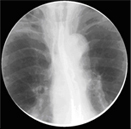

• 식도조영술

식도 점막의 변화를 관찰함으로써 식도암의 모양, 크기, 위치 등을 평가하고, 주위 기관과의 관계를 확인합니다.